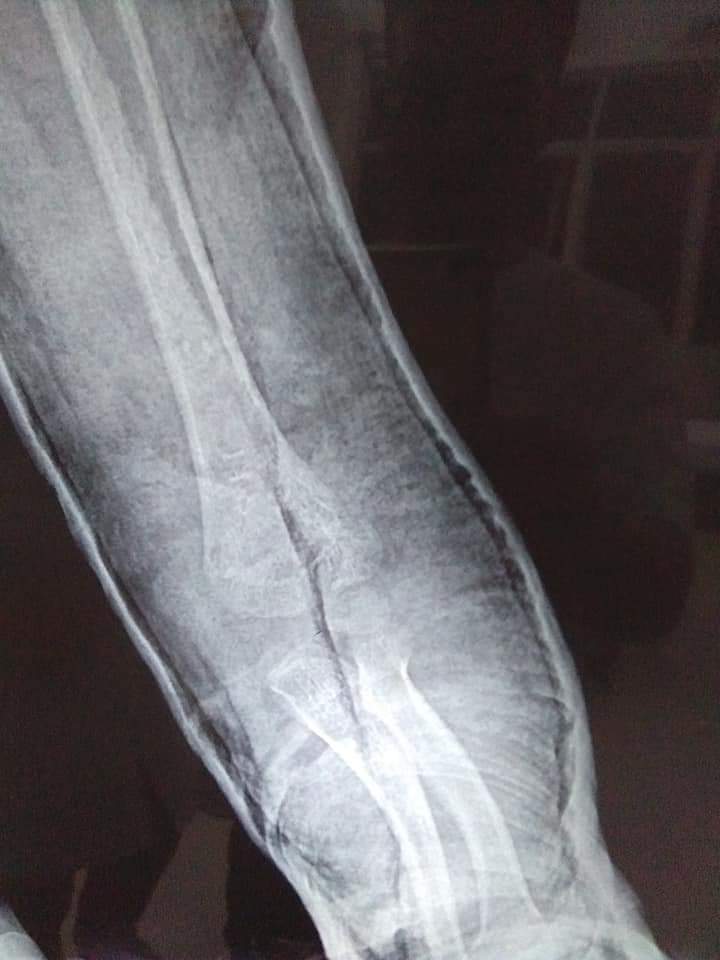

Những hình ảnh trước và sau bó bột tại Trung tâm y tế huyện Nghi Xuân

Hình ảnh trước nắn

Hình ảnh sau nắn